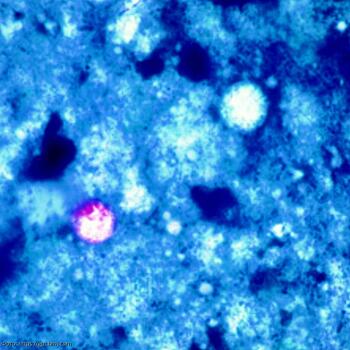

По словам представителей здравоохранения США, в последние месяцы в Массачусетсе резко выросли инфекции, вызываемые кишечным паразитом Cyclospora cayetanensis. Симптомы обычно включают водянистую диарею, потерю аппетита, спазмы в животе, тошноту и длительную усталость. Согласно информации, поступившей в распоряжение ИА «Экспресс-Новости» от представителя Департамента здравоохранения штата Массачусетс, с мая текущего года в регионе выявлено более 100 человек, страдающих от паразита Cyclospora. Это количество случаев намного выше, чем обычно; за последние три года в штате ежегодно регистрировалось только 18-33 случая. Одноклеточный паразит, Cyclospora cayetanensis, как правило, передается через загрязненную пищу. Однако представители здравоохранения до сих пор не определили источник пищи, ответственный за вспышку в Массачусетсе. И это притом, что инфекции паразитом наиболее распространены в тропических и субтропических странах. Но в Соединенных Штатах, по данным Центра по контролю и профилактике заболеваний (CDC), вспышки болезни, известной как циклоспориаз, были связаны с импортными свежими продуктами, в том числе малиной, базиликом, горохом, салатом мескун и кинзой. Отдельно ИА «Экспресс-Новости» заостряет внимание на том, что Массачусетс – не единственный штат, в котором в этом году отмечается всплеск заболеваемости Cyclospora. Официальные лица в Вирджинии расследуют десятки предполагаемых случаев заражения паразитом. Во всяком случае, именно об этом сообщает The Washington Post. Да и в штате Мэриленд официальные лица подтвердили 42 случая заболевания циклоспорами, большинство из которых произошло в последние две недели. Но и здесь не совсем ясно, связаны ли все эти вспышки. При этом эксперты CDC уже бьют тревогу, поскольку как минимум 11 штатов США уже сообщили о случаях Cyclospora. И это в период с 1 мая по 27 июня.